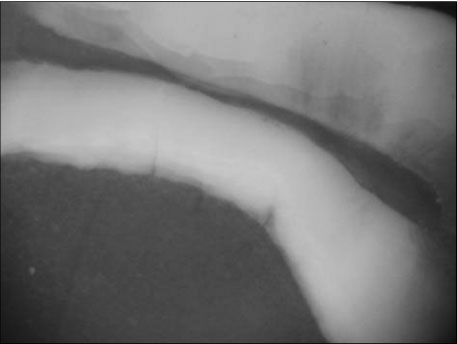

Figure 4

Photograph of section with no isthmus (×40)

Figure 4 Photograph of section with no isthmus (×40)